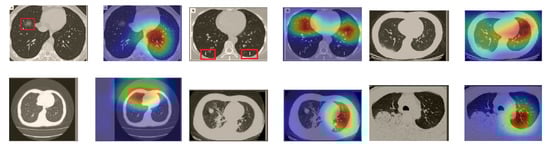

In order to investigate the capacities of the different models to accurately localize identical or similar important regions, we employed the model with the lowest accuracy, i.e., SqueezeNet, which was fine-tuned on the SARS-COV-2 dataset to classify the unseen CT images taken from [61,62]. Moreover, we provide the Grad-CAM localization maps for a direct comparison. Figure 16 illustrates CT images, which represent the first two rows in Figure 15, and their corresponding localization maps. For most of the cases, both models looked exactly at similar regions representing the COVID-19 manifestations. However, for some images, SqueezeNet looked at irrelevant regions, such as the top left corner.

Figure 16.

Grad-CAM visualizations for the same CT images in the first two rows of Figure 15. The CT images were correctly identified by SqueezeNet as COVID-19 cases with relevant localization of the disease-related regions.

Although we trained our models using CT images where both lungs are visible in the scans, we tested them on some external CT scans where only one lung is visible. The CT scans were extracted from the paper [61] and show different CT manifestations of COVID-19 marked by red squares or white arrows. Our models were able to classify them correctly as COVID-19 cases. Intriguingly, when applying Grad-CAM we can see from Figure 17 that all regions of abnormalities are accurately localized. This also proves the potential of our models to detect COVID-19 abnormalities in CT images outside the dataset used for training.

Figure 17.

Example of annotated CT scans with different manifestations of COVID-19 taken from [61], and their corresponding localization maps. Our models were able to identify them as COVID-19 cases and accurately localize their COVID-19-associated regions.